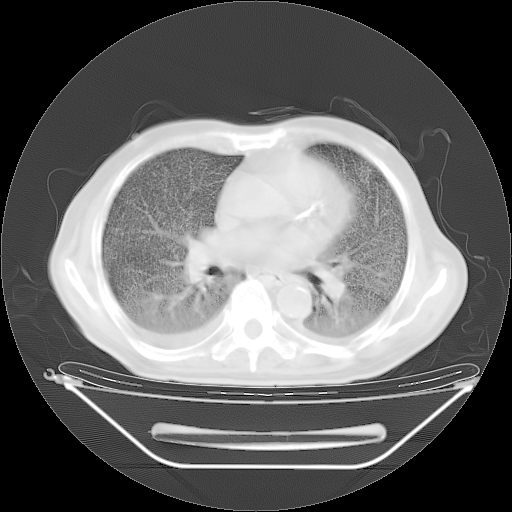

今天复查肺部CT,发现双肺广泛磨玻璃样改变。所以我把3月19日和5月9日相隔50天的肺部CT上传。请大家会诊。

2009年3月19日肺部CT片。

2009年3月19日肺部CT

大致读了系列胸部CT:纵隔窗无明显异常,肺窗:从4、27至今:主要是双肺中下野外带可见毛玻璃样改变,目前处于急性肺泡炎阶段,至于原因考虑1、结替组织或胶原血管性疾病所致?2、恶性疾病如恶组在肺部所致的表现或细支气管肺泡癌?3、药物或其它原因如肺蛋白沉着症所致肺泡炎目前不太可能?总之,明天就去请我院的呼吸科、感染科、血液科和临免专家会诊哈。